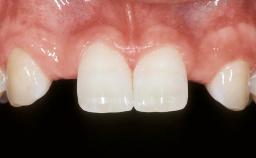

| Case Type | Extended Space |

| Jaw | Maxilla |

| Area | Anterior |

| # of Teeth | 4 |